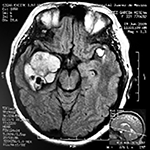

EJEMPLO DE CASO CLÍNICO (9)

Paciente masculino de 34 años de edad, quien presenta crisis convulsivas parciales motoras de brazo y hemicara derecha, secundariamente generalizadas, posteriormente hemiparesia 4/5 para hemicuerpo derecho.

La TAC muestra un área hiperdensa a nivel frontal izquierdo heterogénea que no refuerza con medio de contraste.

LA RMN muestra una lesión bien circunscrita frontal parasagital izquierda con edema perilesional, hiperintensa en T1 y T2, de contenido sólido y quístico, con poca captación del medio de contraste.

Se realizó craneotomía frontal para abordaje interhemisférico anterior.

Se realiza resección total de la lesión de contenido hemático oscuro-verdoso, consistente en un angioma cavernoso. La RMN postoperatoria se observa solo la brecha quirúrgica sin evidencia de lesión.

En el postquirúrgico el paciente desarrollo síndrome frontal lateral, que se controló con Risperidona y remitió después de tres semanas, las crisis convulsivas remitieron y el medicamento se disminuyó de manera paulatina (figs. 4 y 5).

Figura 4:

Imágenes prequirúrgicas y postquirúrgicas de lesión multiloculada del caso 9.